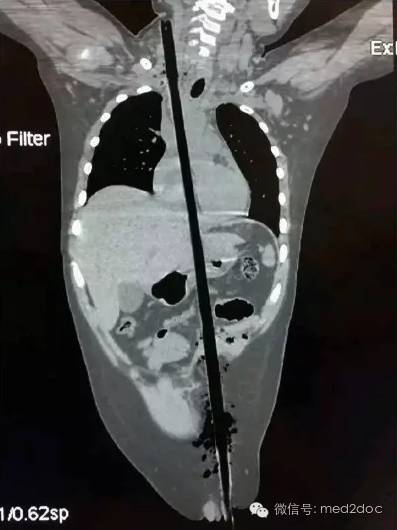

据齐鲁医院报道,最近约30名专家联手执刀,历时7个小时……成功救治1例1.5米钢筋从阴部贯穿头顶的贯通伤,患者奇迹生还。

6月14日下午3点多,济南一名中年男子从5米高空坠落,地上正好有一竖起的钢筋,这根钢筋从男子的阴部直穿头顶。患者是由一根粗约1.5厘米的钢筋从阴部直插穿头顶,阴部以下露出长约四十厘米的钢筋,头顶上穿出长约五十厘米的钢筋,男子*体下**和脸部都留着鲜血,场面触目惊心。

经过CT等全方面检查后,确定钢筋已贯穿男子的泌尿、腹部、胸部、口腔、鼻腔、脑部等具体部位。钢筋从男子的右阴囊插入,途径泌尿系统,伤及腹部的肝脏,紧贴颈动脉贯穿而过。从咽喉直插入口腔,伤及舌头,从上颚经鼻腔,插入大脑,钢筋从头顶穿出。

术中,多科室医生合作,同时将伤者的头颅、胸腔、腹腔打开,在完全暴露的情况下取出钢筋。经过7个多小时,手术在15日凌晨1点多结束,钢筋被顺利取出,测量长度约1.5米。男子性命被保住,这也创造了医学的奇迹。